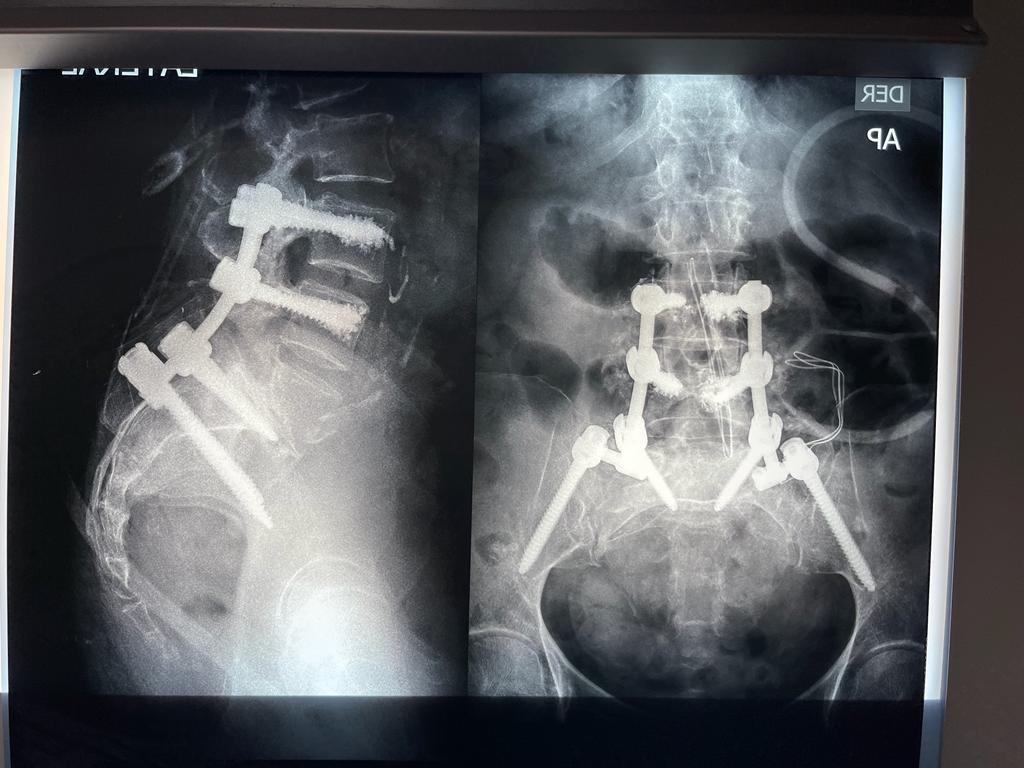

4. Fusión Vertebral (Lumbosacra o Cervical)

Cirugía que une dos o más vértebras para estabilizar la columna y aliviar el dolor.

Fusión Vertebral (Cervical o Lumbosacra)

Es un procedimiento quirúrgico que busca estabilizar la columna vertebral uniendo de forma permanente dos o más vértebras. Se utilizan tornillos, barras y, en ocasiones, una caja intersomática con injerto óseo, para que las vértebras se fusionen en una sola unidad sólida.

¿Cuándo se indica?

- Espondilolistesis (desplazamiento vertebral)

- Inestabilidad vertebral causada por degeneración

- Fracturas vertebrales traumáticas

- Enfermedades degenerativas del disco

- Deformidades como escoliosis o cifosis

- Cirugías previas fallidas

¿Qué se logra?

- Estabilidad de la columna

- Reducción del dolor por movimiento excesivo

- Prevención de daño neurológico progresivo